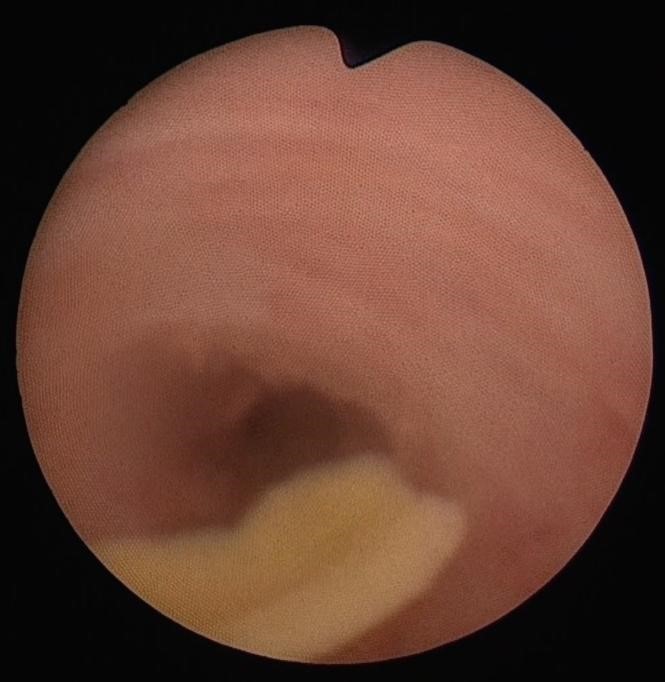

膵液が胆汁と交じることで結晶ができ(これはタンパク栓といわれています)、この結晶が胆管や膵管の通り道をふさぐことで、腹痛、肝機能異常、高アミラーゼ血症などが引き起こされます。つまり、先天性胆道拡張症の臨床症状は、ほとんどが膵・胆管合流異常から来ています。

先天性胆道拡張症の症状である腹痛や肝機能異常、高アミラーゼ血症は、タンパク栓が胆管や膵管に詰まり、胆汁や膵液がたまって胆管・膵管の内圧が上昇することで起こります。膵・胆管合流異常があった場合でも、このタンパク栓が悪さをしない限り、ほとんど症状が現れません。

まれにタンパク栓によって膵管・胆管の閉塞が持続すると、黄疸や胆管炎が悪くなり、胆管内の圧上昇と炎症が重なって、胆管の穿孔(穴が開くこと)を起こし、さらに強く腹痛を起こすこともあります。